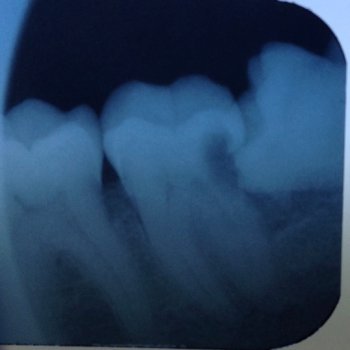

An X ray of a wisdom tooth tilted forwards, growing into the next tooth and causing a cavity.impacted wisdom tooth

In the image above,

the wisdom tooth on the right is lying on its side, jammed up against the next tooth, and it has caused a cavity in the side of the neighboring tooth.